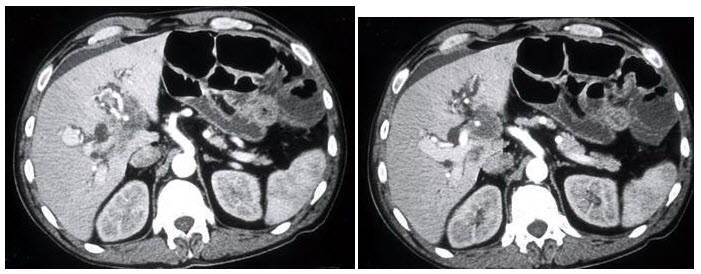

患者溃疡性结肠炎并最近黄疸发作,结合图像,最可能的诊断为()A: 胆管癌B: 肝细胞癌C: 肝脓肿D: 肝炎E: 胆囊癌

患者溃疡性结肠炎并最近黄疸发作,结合图像,最可能的诊断为()

- A: 胆管癌

- B: 肝细胞癌

- C: 肝脓肿

- D: 肝炎

- E: 胆囊癌